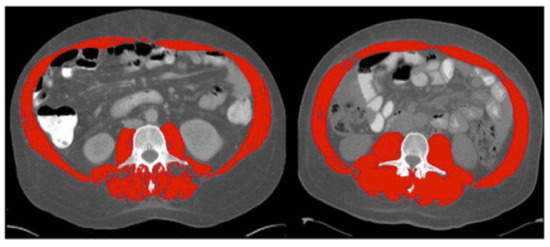

Sarcopenia was first termed in 1989 by Rosenberg et al. as a muscle loss in the aging population [19]. Although several definitions coexist, sarcopenia’s well-adopted description is an age-related process characterized by progressive loss of skeletal muscle mass and function [10]. Several assessment tools can be utilized to assess muscle mass and function (Table 1). To determine the muscle mass, anthropometric measurements, such as the thickness of the skin fold, mid-upper arm muscle circumference (MAMC), and calf circumference have been tried in the past and found to be inaccurate; therefore, these methods are not recommended [20]. Imaging such as computed tomography (CT) at the level of the third lumbar vertebra to assess skeletal muscle index (SMI) (cut-off value of <50 cm2/m2 in men and <39 cm2/m2 in women) and magnetic resonance imaging (MRI) have been used effectively to differentiate between muscle, fat and other soft tissues. However, due to risk of radiation and/or cost, these tests have not been widely used in routine clinical practice [20,21,22] (Figure 1). Instead, dual-energy X-ray absorptiometry (DEXA) is generally recognized as the gold assessment tool to assess the muscle mass in most cases, due to its low cost, low radiation risk of radiation, and reasonable accuracy [23]. Bioimpedance analysis (BIA) can be also used as an affordable alternative method to DEXA [23]. Lastly and importantly, it should be noted that the accuracy of both BIA and DEXA in measuring muscle mass requires patients to be well hydrated prior to undergoing these tests.

Figure 1. Computed tomography (CT) images at the third lumbar vertebra comparing two patients with cirrhosis and same body mass index but one has sarcopenia and other is not. Left image shows sarcopenia with L3mi of 49.82 cm2/m2. Right image shows non-sarcopenia with L3mi of 70.8 cm2/m2. These abdominal CT images were utilized by Montano-Loza et al. in 2012 and cutoff-values offered by Baumgartner et al. in 1998. Red color denotes abdominal wall muscle, psoas and paraspinal muscles. (Used with permission from Elsevier.).